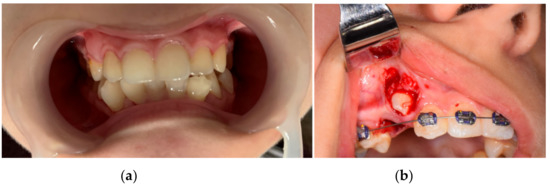

Front, left, and right profile photos; intraoral photos in occlusion; and photos from the time of 1.3 surgical exposure and extraction for orthodontic purposes of 1.4 were taken. Figure 1 and Figure 2 show images of the patient.

Figure 2. Intraoral photos in occlusion (a) and from the surgical intervention (b).